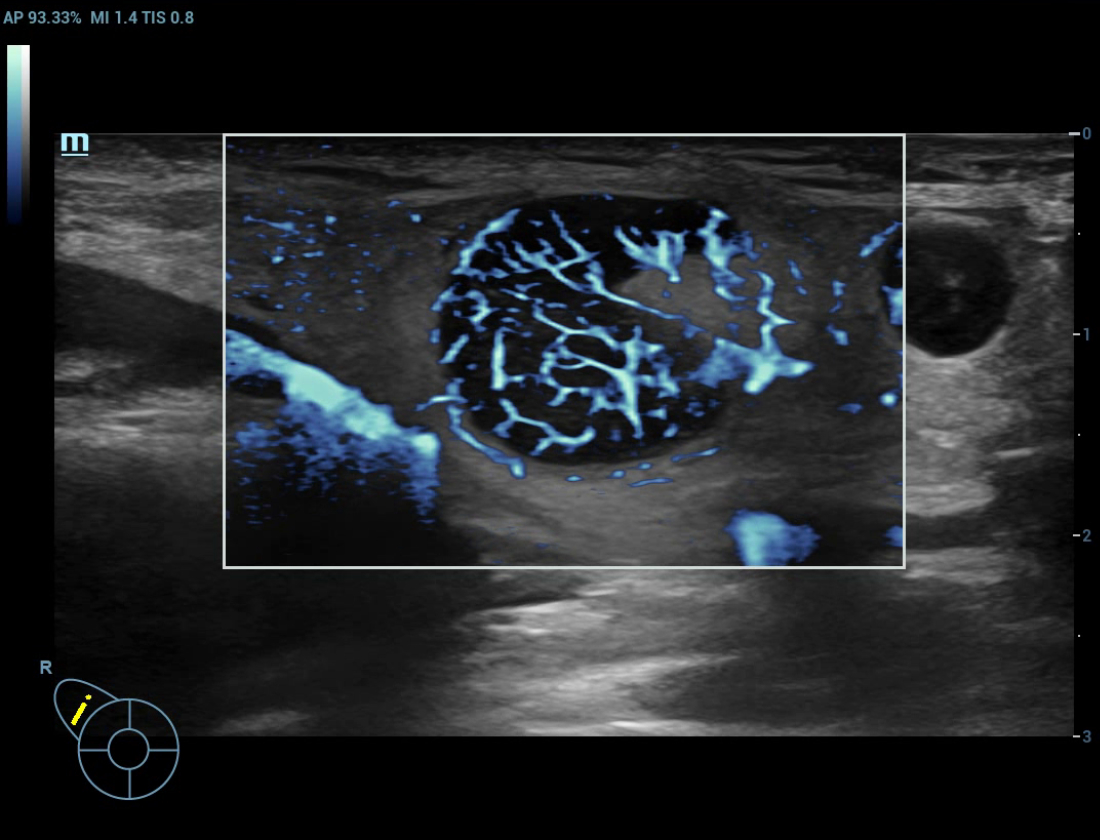

Glazing Flow em fluxo de varicocele

Angiografia ultramicroscû°pica (Ultra Micro Angiography, UMA)

UMA aumenta a confian?a diagnû°stica ao expandir a visibilidade dos fluxos sanguûÙneos atûˋ o nûÙvel de vasos minû¤sculos, com sensibilidade e resolu??o superiores.

pUMA ã Massa mamûÀria

cUMA ã Massa mamûÀria

Massa mamûÀria